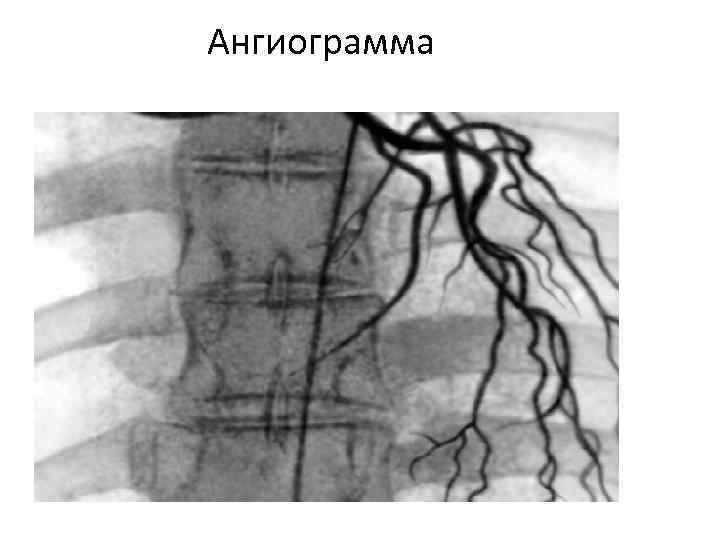

Ангиограмма